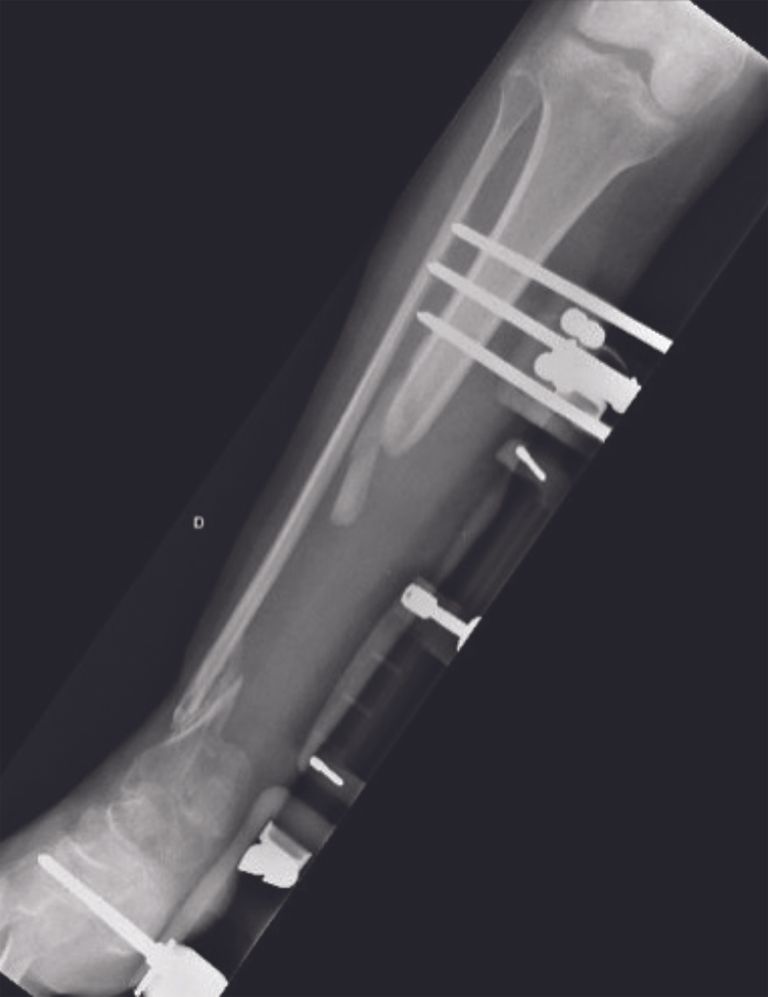

Gustilo III open fractures secondary to high-kinetic trauma pose two main treatment problems. Skin opening and injury to the soft tissues lead to a high risk of infection. Fractures, in particular those of the leg, may be accompanied by a major bone defect, requiring potentially complex bone reconstruction that may not be feasible at an early stage. In these circumstances, the use of a temporary antibiotic bone cement spacer provides benefits in the management of these two problems. When extensive soft tissue lesions associated with bone defects of varying dimensions are present (Fig. 1 and 2), amputation may be discussed as a salvage procedure.

For these reconstruction cases many surgeons prefer the Masquelet technique in this situation. Following emergency care, the first surgical stage consists of bone debridement, inserting an antibiotic bone cement spacer and immobilizing the limb with an external fixator (or performing a temporary osteosynthesis) (Fig 3). Once the fracture location is stabilized, the soft tissue lesions can be managed, by extensive debridement followed by flap coverage, and treating any infection with local and systemic antibiotics. The Masquelet technique builds an induced membrane around the cement spacer within a month.